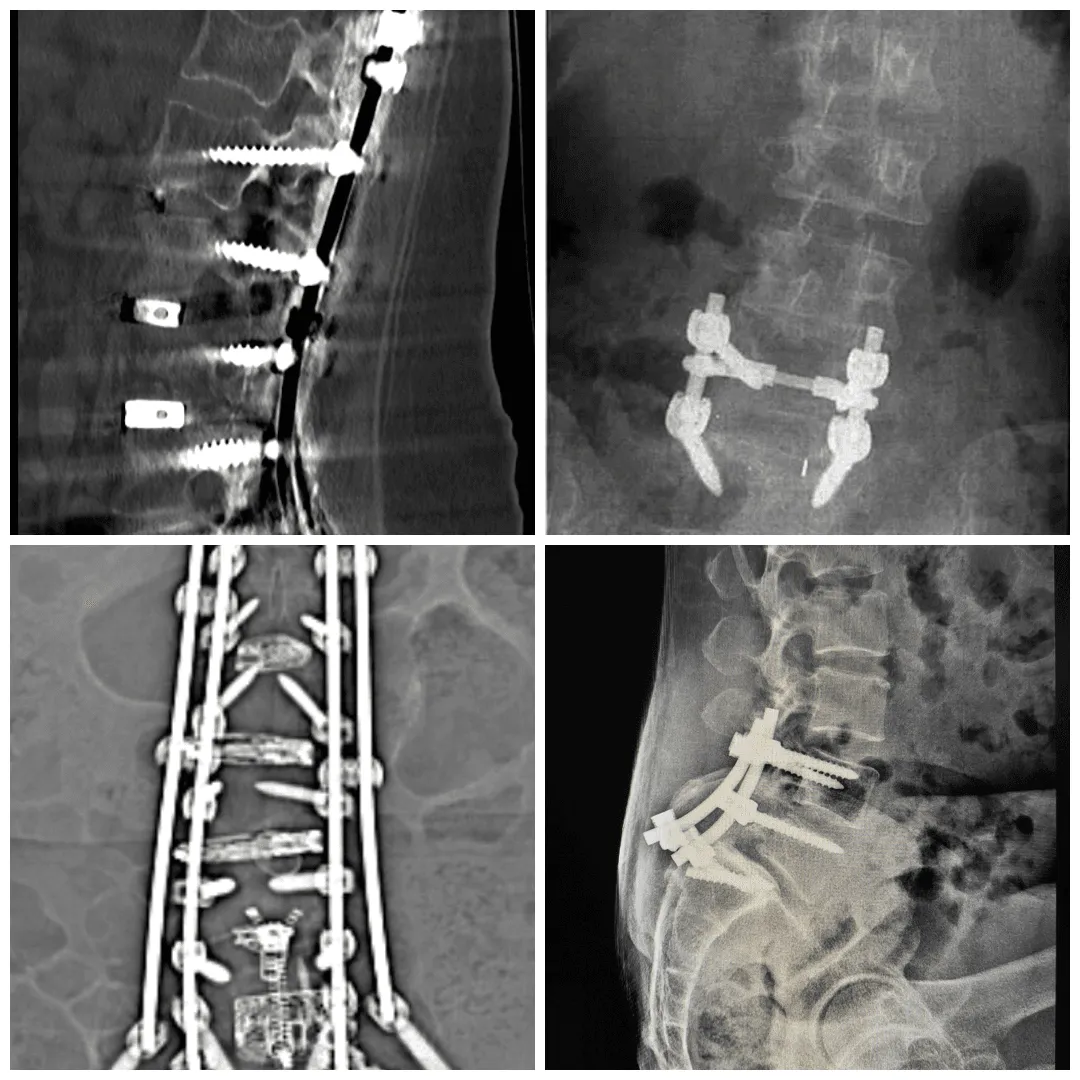

2. Spinal Fusion Surgery: Understanding the Traditional Approach

During spinal fusion surgery, the surgeon permanently connects two or more vertebrae (the bones that make up the spine) together. When fused, these vertebrae heal into a single solid bone. This surgical technique mimics the natural healing process of broken bones.

The spine consists of a disc space in front and paired facet joints behind. Whenever you move your spine, these structures allow motion. During fusion, vertebral segments are joined using a bone graft to stop motion at one or more vertebrae. The bone graft is placed between vertebrae and grows to join the segments together.

Metal plates, rods, or screws are used to ensure correct bone graft growth and healing. The fusion process typically takes 3-6 months as the bone graft grows to form one solid bone.

Different Types of Spinal Fusion

Anterior Cervical Discectomy and Fusion (ACDF): A neck surgery where the surgeon approaches the spine through the front of the neck, removes the damaged disc, and fuses vertebrae with a metal plate.

Posterior Cervical Discectomy and Fusion (PCDF): Identical to ACDF but accesses the spine through the back of the neck using screws and rods.

Transforaminal Lumbar Interbody Fusion (TLIF): A lumbar fusion through the back of the spine where an interbody spacer and bone graft are inserted into the disc space.

Extreme Lateral Interbody Fusion (XLIF): Accesses the lumbar spine from the patient’s side. Often recommended for lumbar disorders like scoliosis and spondylolisthesis.

Anterior Lumbar Interbody Fusion (ALIF): Uses an anterior (abdominal) approach to fuse lumbar vertebrae. Often used when multiple vertebrae are being fused. This surgery has been reported to carry the highest risk of complications among lumbar fusion techniques.